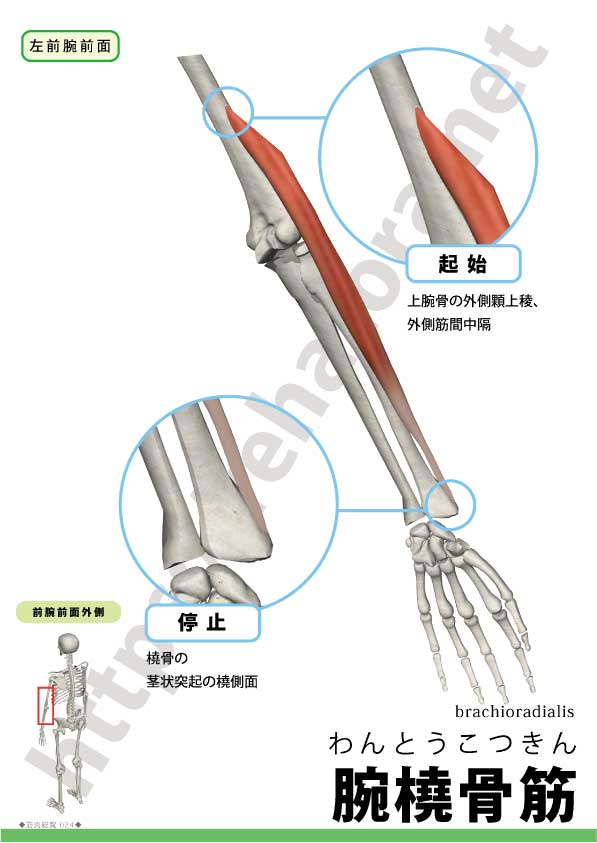

腕橈骨筋は前腕前外側を走る肘屈筋。名前の由来は brachium(腕)+radius(橈骨)。

| 起始 | 上腕骨外側顆上稜(近位)・外側筋間中隔 |

| 停止 | 橈骨遠位外側面(橈骨茎状突起近位) |